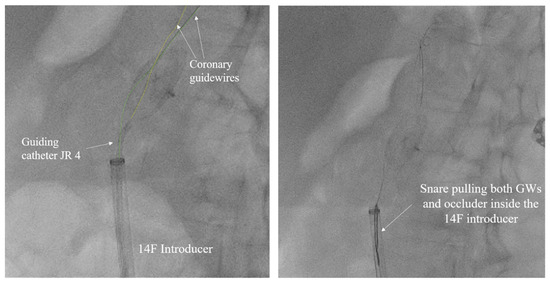

The left common femoral artery (CFA) was promptly punctured, followed by the placement of a 14F introducer. Several attempts were undertaken to recapture the right atrial disc button of the PFO occluder using a 15 mm Amplatz Goose Neck snare (Medtronic, Minneapolis, MN, USA), but these efforts were unsuccessful. The position of the device, trapped within the aorta, with the right atrial disk button opposite to the aortic wall, disabled access to the device even with a 6 F guiding catheter Judkins right (JR) 4 used to navigate and reach the occluder button. This step was succeeded by the introduction of two coronary guidewires with higher tip loads, namely the Pilot 150 (Abbott Vascular, Santa Clara, CA, USA) and Samurai RC (Boston Scientific, Marlborough, MA, USA), one through the JR 4 guiding catheter already positioned and the second one directly through the 14F introducer. These wires were subsequently maneuvered, one by one, through the mesh of the PFO occluder (Figure 5). The JR 4 guiding catheter was withdrawn, and a 15 mm Amplatz Goose Neck snare was introduced through the 14F introducer. Following this, two coronary guidewires were captured proximally to the PFO occluder using a 15 mm Amplatz Goose Neck snare and subsequently pulled, facilitating the partial retraction of the PFO occluder into the 14F introducer (Figure 5, Video S1).

Figure 5.

Amplatz Goose Neck snare complemented with two coronary guidewires (GWs) in a unique system for occluder retrieval.

In our case, we employed a unique system consisting of a 15 mm Amplatz Goose Neck snare, which was complemented with a dual-wire unit featuring Pilot 150 and Samurai RC coronary wires. These components were integrated into a sophisticated and efficient snaring technique, which was eventually followed by a CFA arteriotomy.